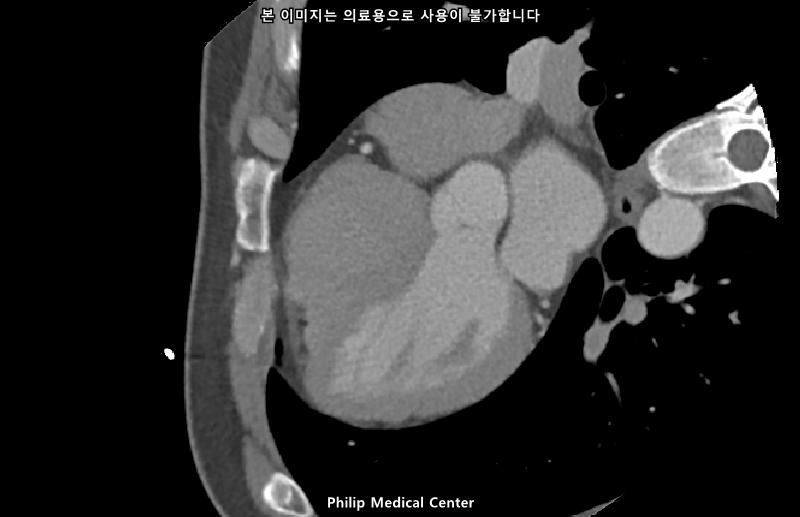

• 4번 째 사진

• 올리신 사진들을 통해서는 폐를 평가할 수 없습니다.

우측 폐첨부에 경미한 섬유성변화와 우중엽에 약 3mm크기의 결절이라는 것은 이상 소견이긴 하지만 보통 경과관찰을 하는 소견입니다.